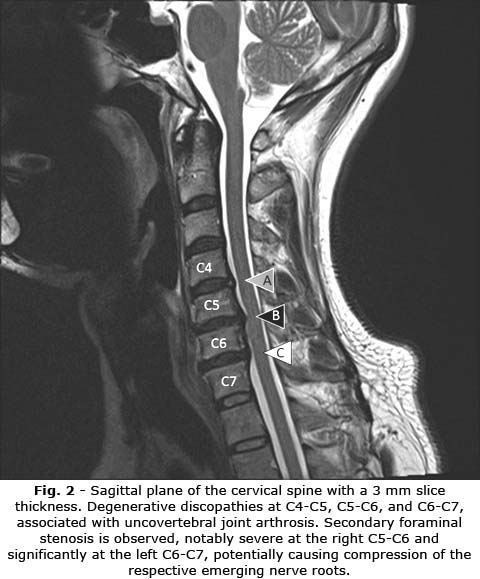

Magnetic resonance imaging of the cervical spine: The cranio-cervical junction was normal. Mild uncovertebral joint degeneration was identified at C4-C5, C5-C6, and C6-C7. Degenerative discopathies were observed in the sagittal plane of the cervical spine (Fig. 2), with a 3 mm slice thickness and degenerative disc disease with protrusions potentially compressing nerve roots was detected.